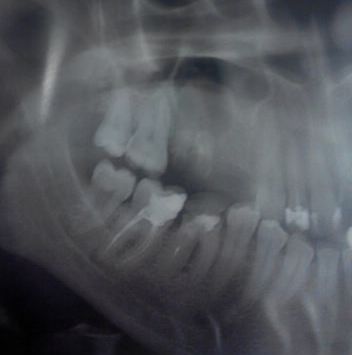

Во время планирования операции для импланта на томограмме обнаружилась киста на ранней стадии под гайморовой пазухой у семерки. Имплантолог говорит, что трогать необязательно, но на вопрос ― будет ли киста развиваться, отвечает утвердительно.

Подскажите, имеет ли смысл заняться кистой сейчас, не дожидаясь тяжелых последствий, и можно ли её удалить без потери зуба?

Киста будет развиваться, и приведёт это к потере зуба. Не трогать можно в случае, если уже сделать ничего невозможно.